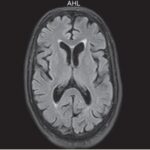

Se pueden mencionar al respecto los estudios que han encontrado en pacientes dependientes al alcohol una disminución del volumen de sustancia gris en el área de la corteza frontal, el hipocampo y el tálamo. El volumen de las sustancias blanca y gris también se puede ver disminuido en el área periventricular, la protuberancia y el cerebelo. Estos déficits de volumen también se han localizado en la corteza prefrontal dorsolateral derecha, ínsula anterior derecha, en el núcleo accumbens y en la amígdala izquierda(16) (ver Imagen 1).